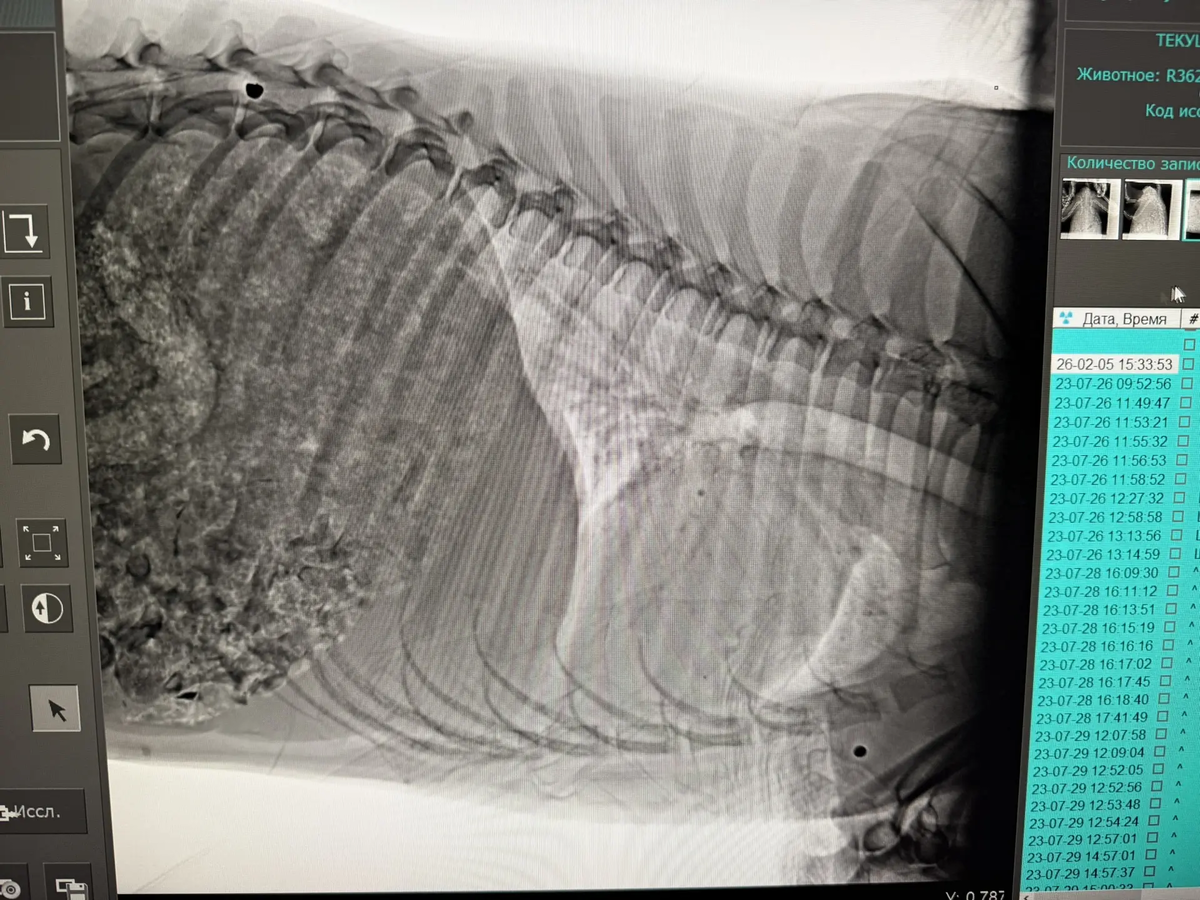

У собачки сохранена чувствительность в лапках, но сами задние лапы уже стёрты и в ранах. Мы сделали рентген (оставались денежки с оплаты аренды) и были в шоке. В очередной раз перед нами собака, в которую стреляли ИЗ ДРОБИ! Таз, брюшко — ВСЁ В ПУЛЯХ! Перелом таза…

А ещё, похоже, ПНЕВМОНИЯ! Нужен кардиолог, травматолог. Нужно сдать кровь обязательно — общий и биохимию, ПЦР. Также у собачки полный желудок КОСТЕЙ.